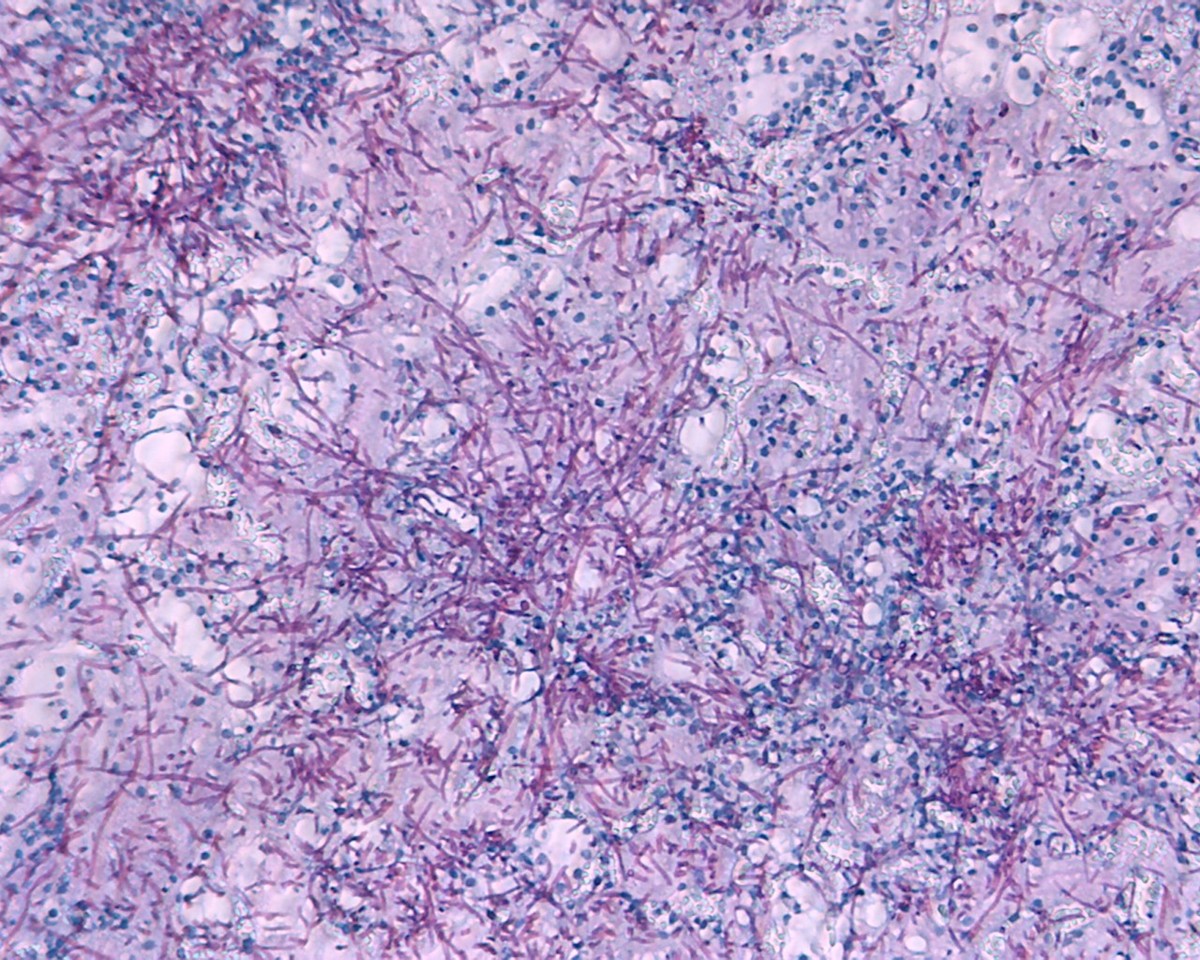

Then we went on to test whether treating mice with β-lactam Abx would promote C. albicans hyphal growth in the gut. We fed β-lactam or non-β-lactam Abx to mice, followed by oral inoculation of C. albicans yeast cells. We then examined the morphologies of C. albicans in feces and the cecum. Strikingly, while all C. albicans cells found in feces and the cecum of control mice were in the yeast form, the majority of C. albicans cells collected from the β-lactam Abx-treated mice were long hyphae. In comparison, none-β-lactam Abx had no significant effect on C. albicans morphology. Furthermore, we demonstrated that the hyphal growth caused β-lactam Abx treatment increased the incidence of systemic dissemination of C. albicans in mice.